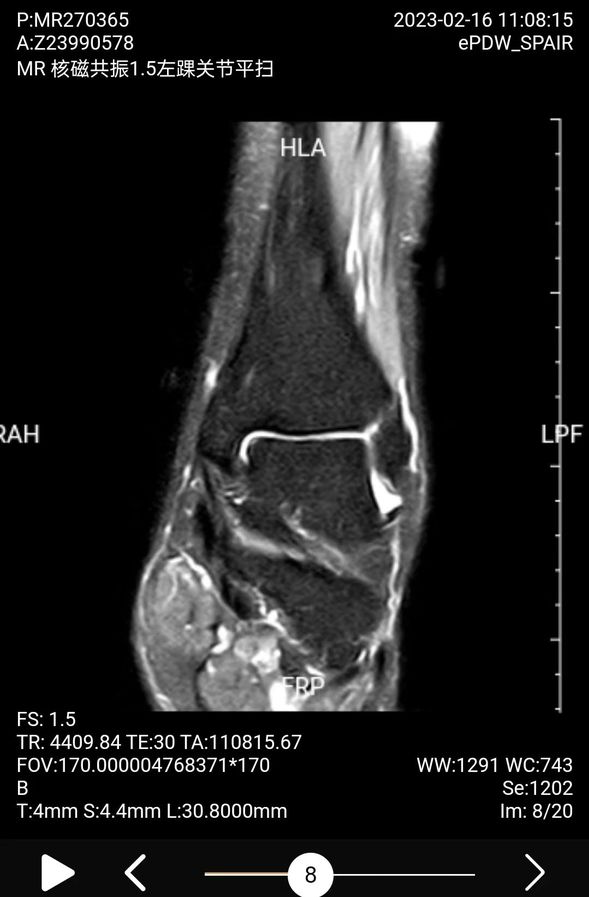

术前踝关节磁共振检查左侧外踝距腓前韧带损伤,信号不连续